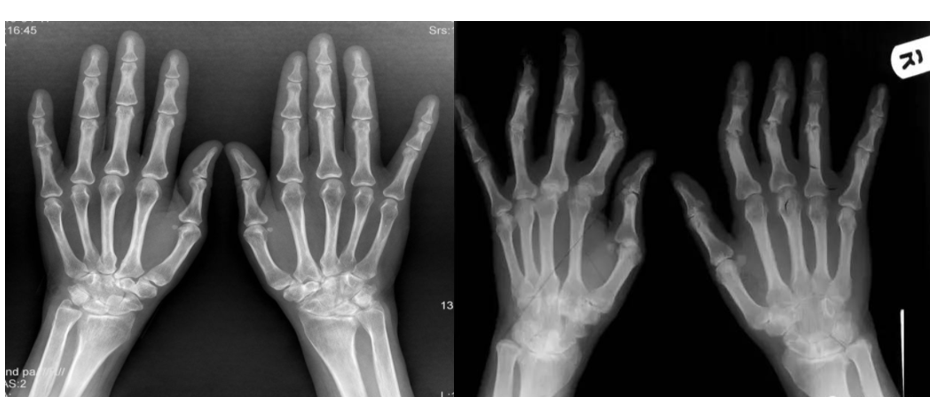

The clinical symptoms are mainly joint swelling and pain all over the body And movement disorders, etc., the condition is extremely serious and may even lead to disability.

The basic pathological changes are synovitis, synovial swelling, exudation, and neutrophil infiltration in the acute phase; hyperplasia and hypertrophy of the synovial membrane in the chronic phase, forming pannus; the latter is the cause of joint destruction, joint deformity, dysfunction, and disease Enter the pathological basis of the irreversible stage.

Successful demonstration of model construction